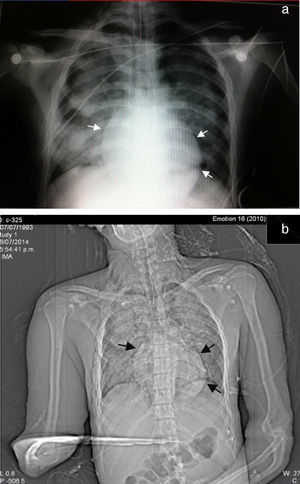

Seventy-two hours after admission, the patient presented subcutaneous emphysema in the anterior chest extending to the neck, a simple CT scan was performed of the chest and abdomen which revealed a pneumomediastinum, bilateral lung contusions and pneumoperitoneum (Figs. 2 and 3). He continued on mechanical ventilation. Oesophageal injury was ruled out by oesophagogram with water-soluble contrast medium, and flexible bronchoscopy ruled out tracheobronchial injury. Furthermore, no signs of peritoneal irritation were found, therefore the Macklin effect was established as the cause of the pneumomediastinum and pneumoperitoneum.

In cases where the chest X-ray is normal (fewer than 10%), the study of choice is CT, which is considered the gold standard, even in patients with suggestive radiological findings.1,10 The Macklin effect appears as a linear collection of air contiguous with the bronchovascular sheath and the characteristic findings of interstitial emphysema due to the Macklin effect present as a triad: (1) interstitial emphysema, (2) to the bronchus, and (3) to the pulmonary blood vessel.3,16 CT has high sensitivity to pneumomediastinum and pneumoperitinoneum (>95%) and specificity (>85%) in order to rule out major injury to the aerodigestive tract. However, the possibility of an oesophageal or tracheal injury should always be ruled out using other diagnostic methods.10

The presence of a pneumoperitoneum is generally associated with perforation of the hollow viscera and therefore requires emergency surgery; in 5–15% of cases it is not the result of visceral perforation and most of the time is associated with medical interventions.17 Mularski et al.17 identified 2 groups as non-surgical causes of pneumoperitoneum: (1) abdominal cause (post-operative air, peritoneal dialysis, endoscopic gastrointestinal procedures), and (2) thoracic cause (mechanical ventilation, cardiopulmonary resuscitation, lung trauma injuries, pneumothorax) which indicate that when abdominal pain and distension are minimal, and when peritoneal signs, fever and leukocytosis are absent, nonsurgical causes should be considered.17,18